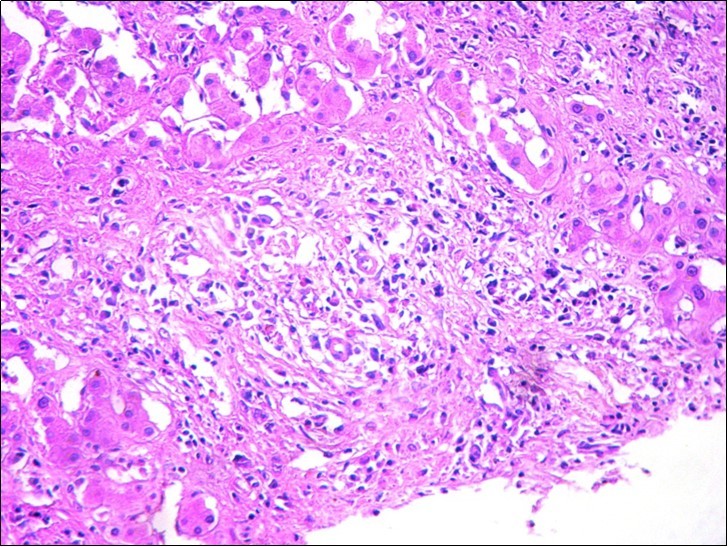

After a multidisciplinary concertation, the hepatectomy was recused because of the size of lesion, the uncertain nature of the lesion and the small remaining liver in case of surgery. The pathological examination was performed again showing inflammatory pseudotumor of the liver (Figure 3). The Polymerase Chain Reaction (PCR) of the specimen was positive. PCR BK made on liver biopsies molecular profile compatible with a hepatic tuberculosis despite the absence of a granulomatous reaction to histology

Figure 3.Hepatic biopsy showing a marked inflammatory reaction with a polymorphic infiltrate (HEx200)

The clinical presentation is not specific and a high degree of clinical suspicion is required to diagnose the entity. There is often abdominal pain with fever associated with a biological inflammatory syndrome 5. Weight loss, jaundice and hepatic failure are very rare. Imaging can play an important role in the detection, characterization, and management of liver tuberculosis 6. Knowledge of the wide spectrum of CT appearances of abdominal tuberculosis should alert the radiologist to consider its diagnosis, especially among high-risk groups of patients, however, the diagnosis remains histological showing a large epithelioid tumour composed of a giant cells with central caseating necrosis. However,the confirmation of mycobacterium in the tissue samples is rare and the sensitivity of the Ziehl stain coloration onthe tissue remains low (20%) 7 as well as culture of tissuesample for mycobacterium tuberculosis (one third of cases). Therefore, the discovery of liver granulomas, even in the absence of caseous necrosis, is accepted as evidence of tuberculosis) 8. During the last two decades, the use of polymerase chain reaction to directly detect the presence of Mycobacterium tuberculosis is increasing and may improve sensitivity rates. (sensitivity 53-92% andspecificity 70%) 9, 10. This technique was usefull to perform diagnosis in our case report. In most cases, the diagnosis is madeon the resected specimen obtained by laparotomy. Thisreflects the difficulty in establishing a correct diagnosisin the absence of extrahepatic involvement.